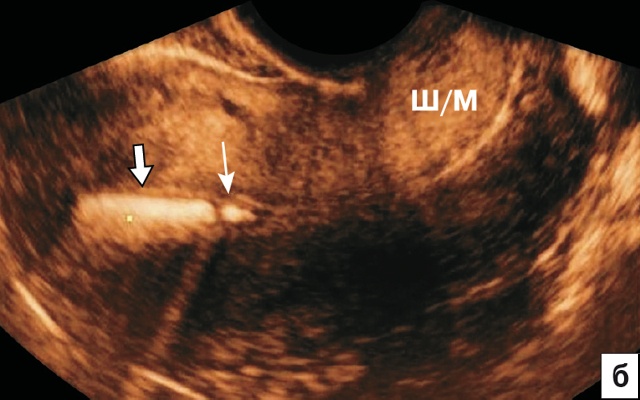

На рис. 2 отражена картина различных ВМС на среднесагиттальном срезе матки при 2D-УЗИ. Для всех Т-образных форм ВМС (включая Мирену) и Multiload стандартной картиной является визуализация гиперэхогенной линейной структуры в проекции полости (рис. 2а). В отличие от Т-образных, Multiload при исследовании в парасагиттальном сечении дает дополнительную специфическую ультразвуковую картину в виде 3–4 продольно расположенных одинаковых гиперэхогенных включений (рис. 2в). Также характерную картину на сагиттальном срезе дают кольцевидные ВМС в виде проксимальной короткой линейной структуры и дистальной отдельной точечной (рис. 2б) и петля Липпеса в виде 4–5 отдельных эхогенных фрагментов (рис. 2г). Кольцевидные ВМС и петля Липпеса в настоящее время практически вышли из употребления.

б) Характерная эхографическая картина кольцевидного ВМС. Длинный гиперэхогенный фрагмент – отражение от стержня (стрелка) и короткий дистальный – фрагмент кольца (тонкая стрелка).